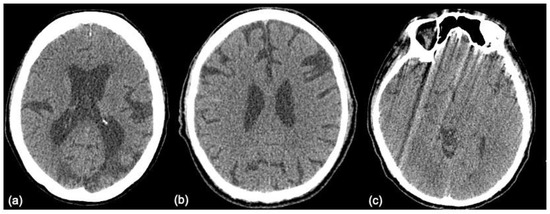

Figure 6. Examples of the false positive images: (a) CVA is misinterpreted as Hx, (b) Hx is misinterpreted as CVA, and (c) Oth is misinterpreted as CVA. CVA = infarction, Hx = hemorrhage, NP = normal, Oth = others.

The images that are false positive are illustrated in Figure 6. However, we cannot provide a clear explanation of why the classification failed, due to the mechanism underlying the “black box”. There is no relationship between size, laterality, location, or augmentation process. It is possible that an increase in data size will achieve better performance.